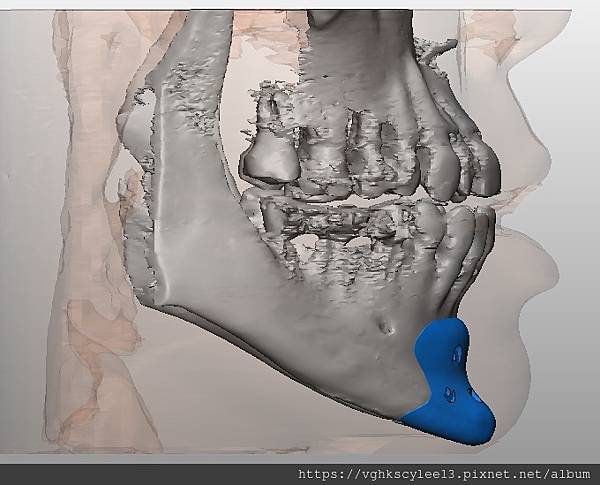

下圖:不對稱下巴骨架,透過列印技術可以做出調整下巴歪斜的假體組合。

歪斜下巴調整性假體設計

下圖範例:歪斜不對稱下巴經3D導航客製化導航矯正性假體